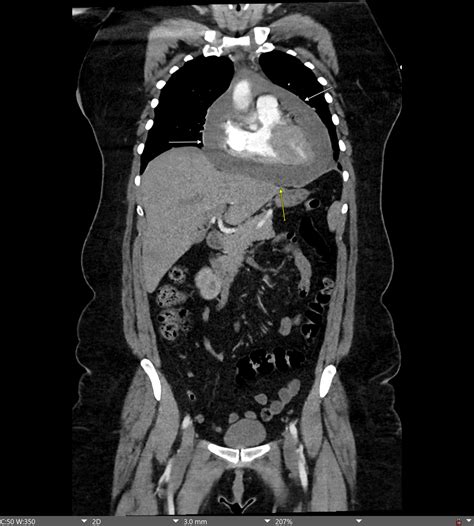

Cardiac tamponade is a critical medical emergency characterized by the accumulation of fluid, blood, or pus in the pericardial sac, which puts excessive pressure on the heart. This pressure restricts the heart's ability to fill properly during diastole, leading to a significant decrease in cardiac output and potential cardiovascular collapse. One of the most vital diagnostic tools available to clinicians in the acute setting is the Heart Tamponade ECG. Recognizing the characteristic patterns on an electrocardiogram can often be the difference between life and death, serving as an early warning sign before more invasive diagnostic imaging like an echocardiogram can be performed.

To grasp why the Heart Tamponade ECG presents with specific findings, one must first understand the mechanical constraints imposed on the heart. When the pericardial space fills rapidly, the intrapericardial pressure rises. This pressure compresses the cardiac chambers, particularly the right atrium and right ventricle, which operate under lower pressures than the left side of the heart. As these chambers struggle to expand, filling is hindered, leading to Beck’s Triad—a classic clinical sign consisting of hypotension, jugular venous distention, and muffled heart sounds.

Because the electrical activity of the heart is independent of the mechanical filling, the ECG records the heart's effort to beat against this external resistance. However, the electrical signals are often altered by the presence of the fluid acting as a physical insulator and the heart's changing position within the fluid-filled sac.